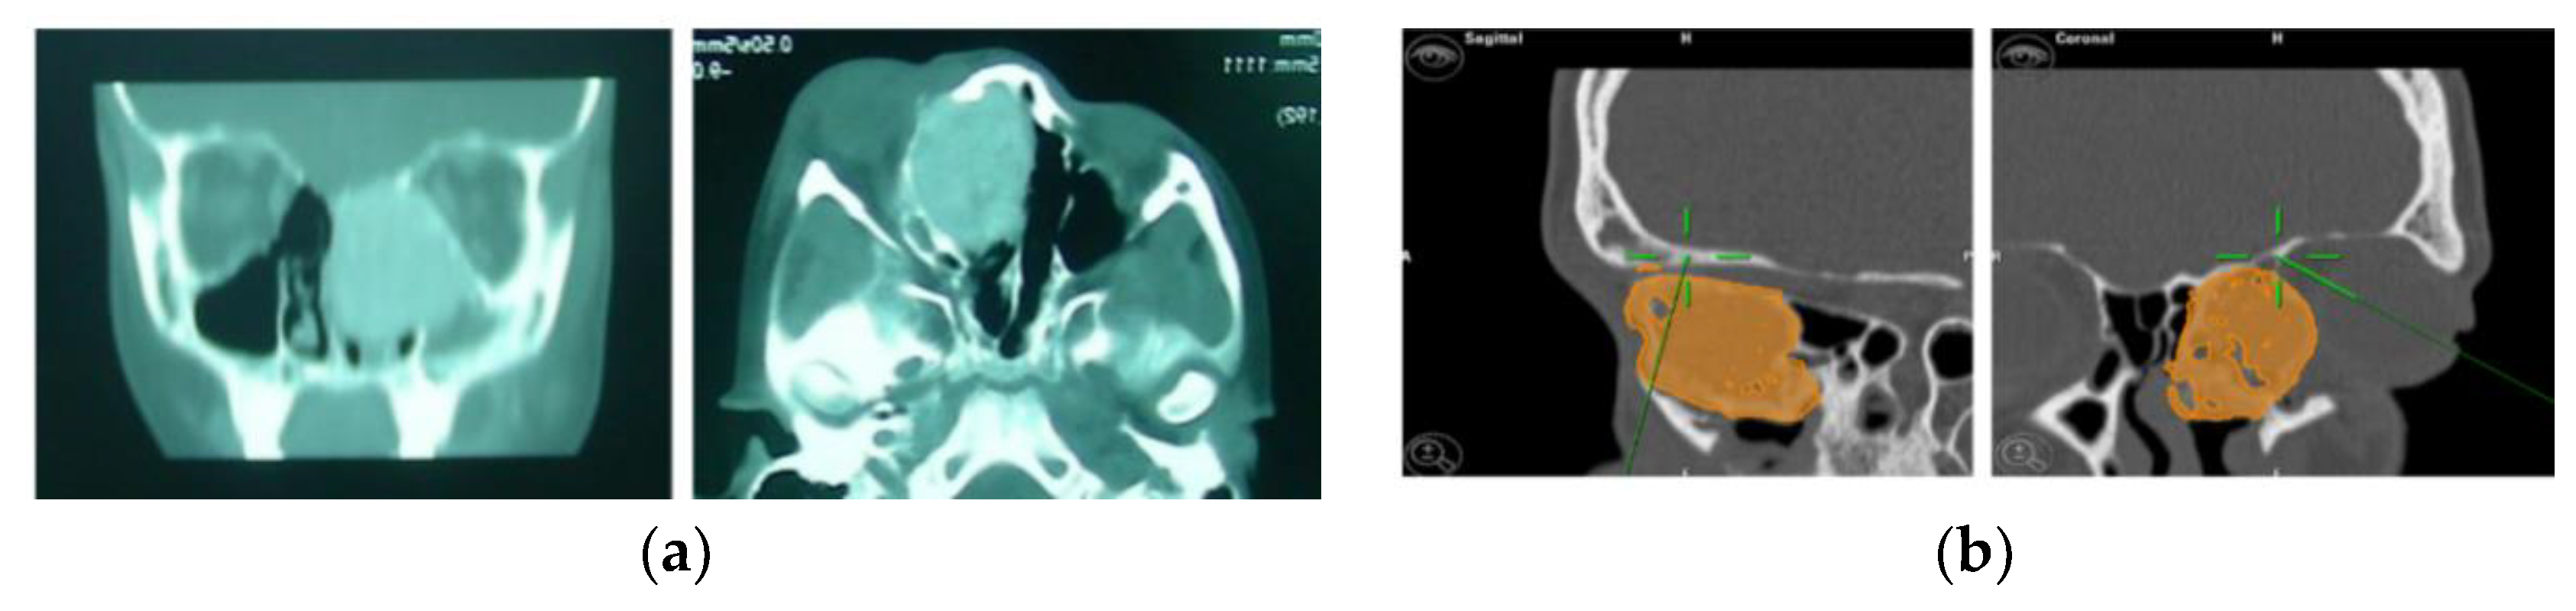

A preoperative CT scan was performed, and the resection margins of the neoplasm were prototyped with the assistance of the iPlan 3.0 software by Brainlab (Figure 5). The operation was performed under general anaesthesia, utilising the navigation system. The DRF system was positioned in the right parietal region, ensuring a navigation accuracy of <0.5 mm. The surgical intervention was performed with a left transconjunctival retrocaruncular approach. The resection was performed using a “piecemeal” technique with a tracked chisel and a mini-saw, while the resection margins were monitored under the guidance of surgical navigation (Figure 6). The instruments were registered by anchoring the three reflecting spheres of the tracking tool to both its handpiece and the edge of the chisel, while the marked tip of the mini-saw served as a reference for navigation. The reconstruction of the medial wall and the left orbit floor was made with a pre-moulded titanium mesh (Figure 7).

Figure 5.

(a) Preoperative CT scan showing the tumour. (b) Virtual planning of resection margins.